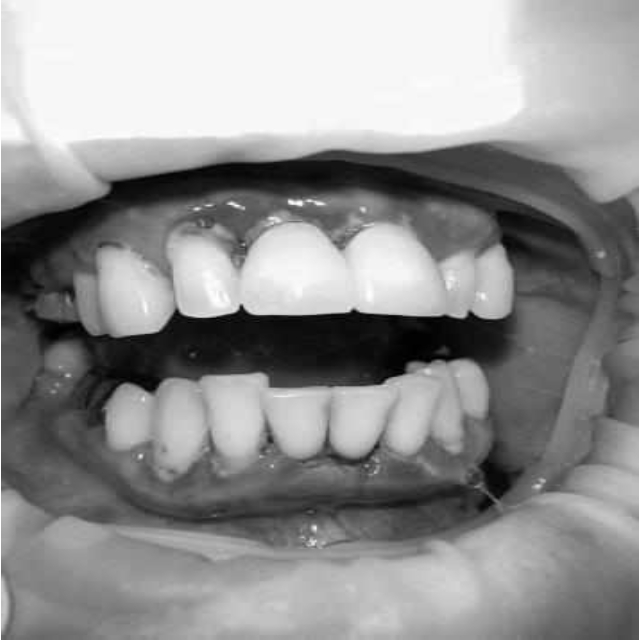

За пародонтологическим лечением обратилась женщина 61 года с жалобами на неприятный запах из полости рта, кровоточивость десен при чистке зубов, подвижность зубов, несостоятельность ортопедических конструкций.

Ранее у пародонтолога не наблюдалась. При осмотре выявлены: неудовлетворительная индивидуальная гигиена полости рта, пародонтальные карманы до 7 мм, обильная кровоточивость и гноетечение из пародонтальных карманов, подвижность зубов 4.2, 4.1, 3.1, 3.2 II степени, обильные над- и поддесневые зубные отложения (рис. 1). На ортопантомограме отмечается резорбция костной ткани до ½ длины корня, очаги остеопороза (рис. 2). Пациенту был поставлен диагноз хронический генерализованный пародонтит тяжелой степени тяжести. При осмотре была составлена пародонтограмма с использованием компьютерного зондирования (рис. 3).

Рис. 1. Внешний вид